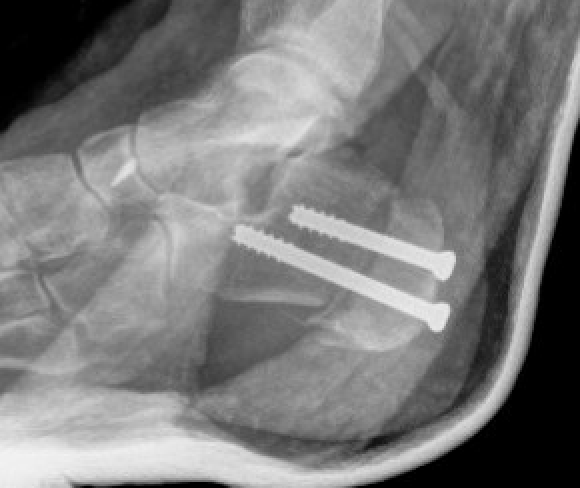

Dwyer lateral closing wedge calcaneal osteotomy

Indication

Fixed hindfoot varus

Technique

Lateral approach

- posterior and inferior to peroneal tendons

- resect lateral wedge of bone

- reduce calcaneal ostoeotmy and fix with screws